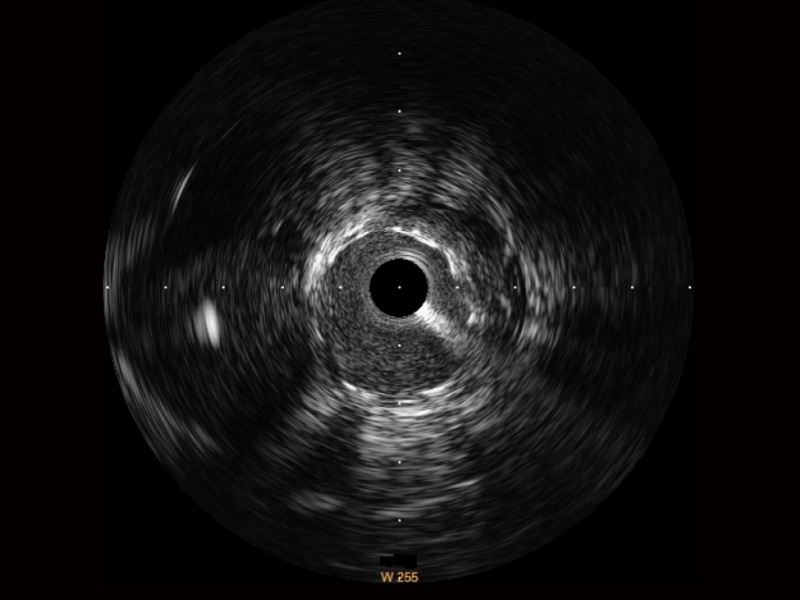

• 乐玩lewin国际宽频IVUS图像

• 传统IVUS图像

对比传统IVUS导管成像,乐玩lewin国际宽频IVUS图像的近场支架梁显影更细腻,远场中膜外血管仍清晰可辨,兼顾远中近,兼顾分辨力与穿透深度